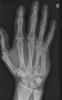

X-ray : metacarpal shaft fracture